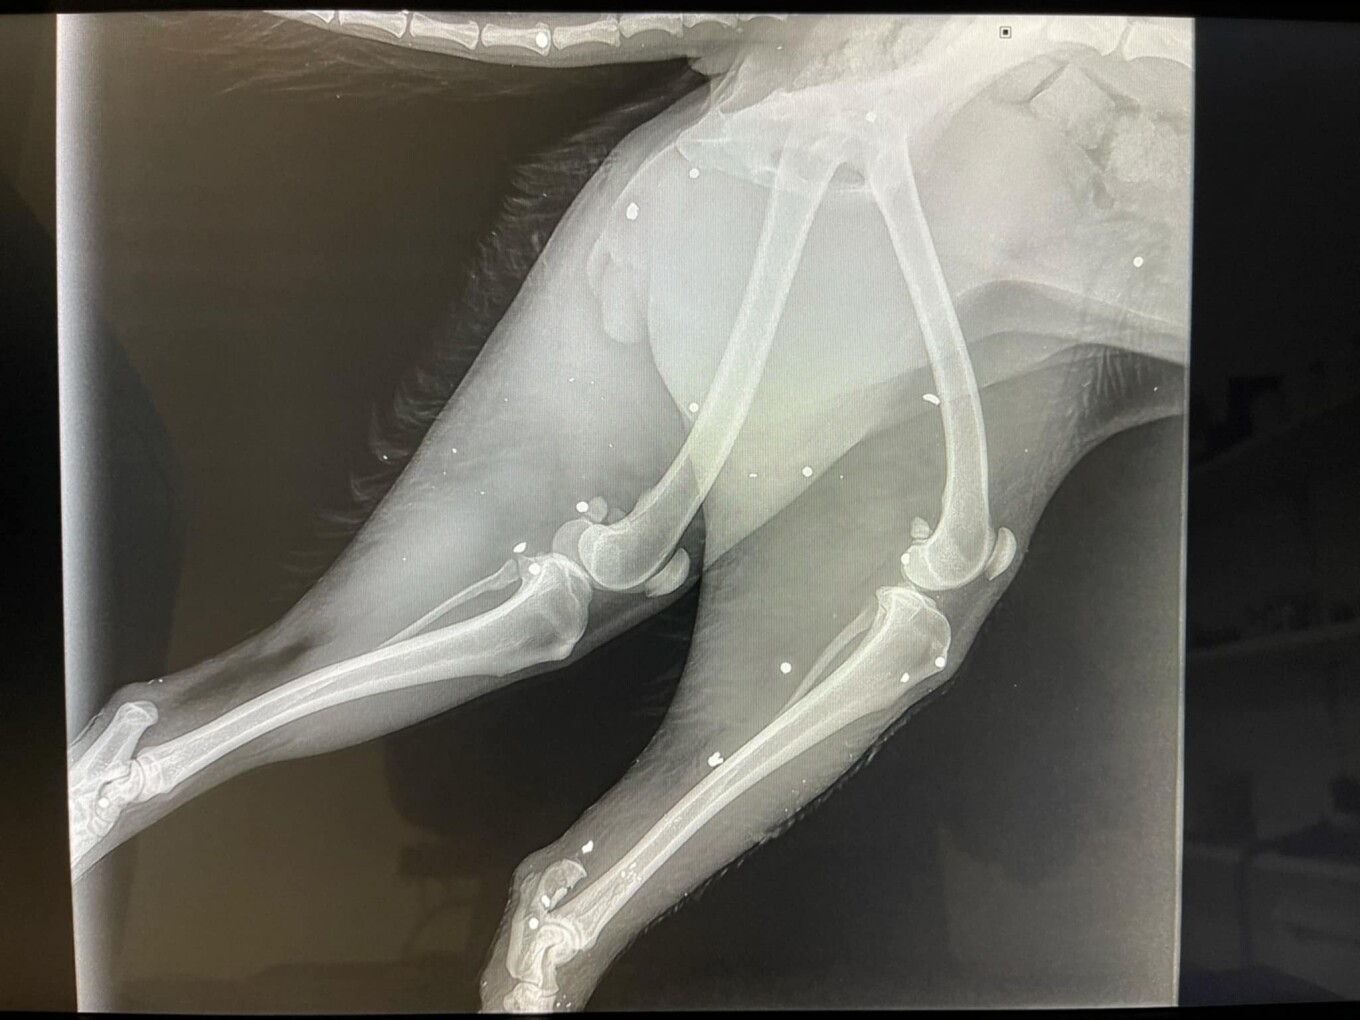

Όπως αναφέρει ο ιστότοπος flashnews.gr, η μικρόσωμη σκυλίτσα, βρέθηκε σοβαρά χτυπημένη, με τα κόκκαλα στο ένα της πόδι να είναι κυριολεκτικά θρυμματισμένα, ενώ στο άλλο πόδι το κόκκαλο φαίνεται εκτεθειμένο.

Παράλληλα, στο σώμα της βρέθηκαν και σκάγια, τα οποία επιβεβαιώνουν πυροβολισμό.